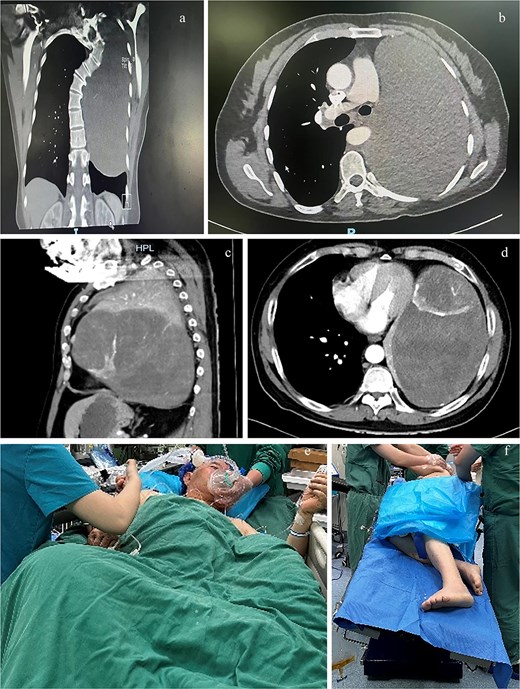

Computed tomography (CT) planes of case 1 in (a) coronal and (b) transverse planes and case 2 in (c) sagittal and (d) transverse planes. The (e) semirecumbent left-tilted posture of case 2 during anesthesia induction and the (f) right lateral decubitus position with the operating bed tilted leftward of case 2 during surgery.

A 48-year-old female patient with 140 cm and 41 kg was admitted with a 1-month history of cough, sputum production, and wheezing. Computed tomography (CT) revealed a solid mass measuring 10.7 × 16.0 × 20.5 cm within the left thoracic cavity (Fig. 1a and b). Bronchial angiography and embolization were performed 2 weeks prior to surgery. Pulmonary rehabilitation exercises were initiated.

A 74-year-old male patient with height 172 cm and weight 74 kg presented with a left thoracic mass identified 7 years prior. Over the preceding 6 months, he experienced abdominal distension, anorexia, wheezing, recurrent lower limb edema, and orthopnea. CT demonstrated a solid mass measuring 11.1 × 19.2 × 23.0 cm occupying the left thoracic cavity (Fig. 1c and d), with rightward cardiac displacement. Vascular embolization was not achieved for the inability to identify the tumor’s feeding vessels and the patient’s intolerance of prolonged supine positioning.

The patient was positioned comfortably in a semirecumbent left-tilted posture (Fig. 1e) during anesthesia. Anesthesia induction was achieved via slow-inhalational administration of sevoflurane (incrementally increased to 5%) combined with intermittent boluses of propofol (1 mg), maintaining spontaneous ventilation. Airway topical anesthesia was administered using the spray-as-you-go technique [3]. A 37 French right-sided double-lumen bronchial tube was inserted and positioned under fiberoptic bronchoscopy guidance ~15 minutes later. The patient was then transferred to the operating bed and gradually repositioned to the right lateral decubitus position with the operating bed tilted leftward (Fig. 1f). Subsequent anesthetic management mirrored that of case 1. The surgery lasted 7 hours. Intraoperative blood loss was 8000 ml, necessitating transfusion of 27 units of RBCs, 5000 ml FFP, one therapeutic dose of platelets, 180 g albumin, 1000 ml of the crystalloid, and 4500 ml of the colloid. Urine output was 550 ml. Following lung recruitment, 30 ml of pink fluid was observed in the airway over a 10-minute period. The patient was extubated on postoperative day 3 and discharged on day 16.